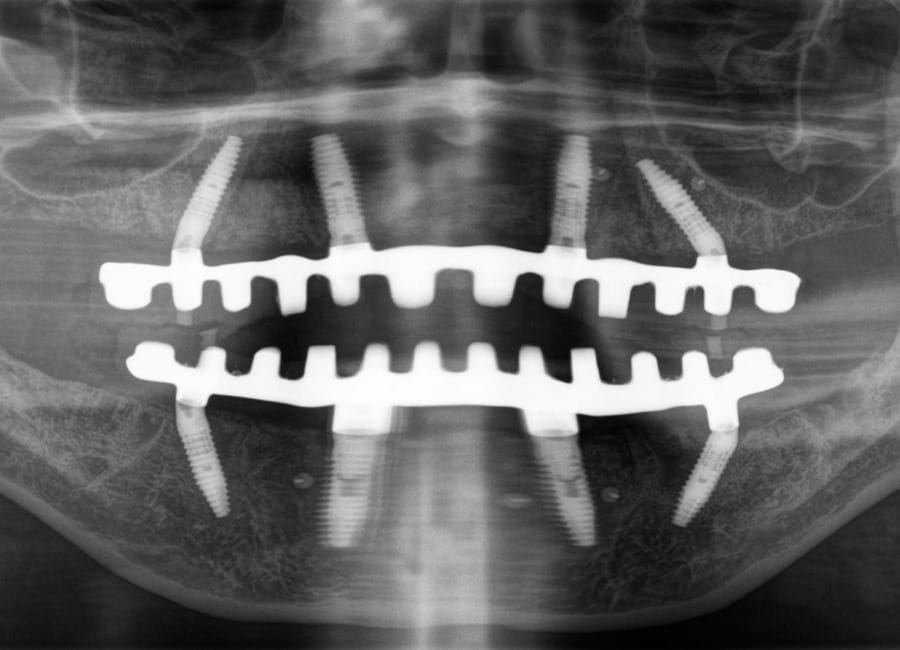

Natalie’s treatment began with a comprehensive clinical assessment, including a review of her medical and dental history, a full examination, and analysis of her functional difficulties such as her tongue habit and altered bite. A 3D cone-beam CT scan was then taken to assess bone quality and volume, identify areas of infection, and map important anatomical structures to ensure safe implant placement.

All data were transferred into digital treatment planning software, allowing virtual placement of implants and collaboration with the dental laboratory before surgery. This enabled careful evaluation of long-term outcomes and ensured the design of provisional and final prosthetics could be completed with precision. Following these discussions, the decision was made to proceed with the Fixed-Teeth-in-a-Day approach using the All-on-4 technique.

Surgical phase